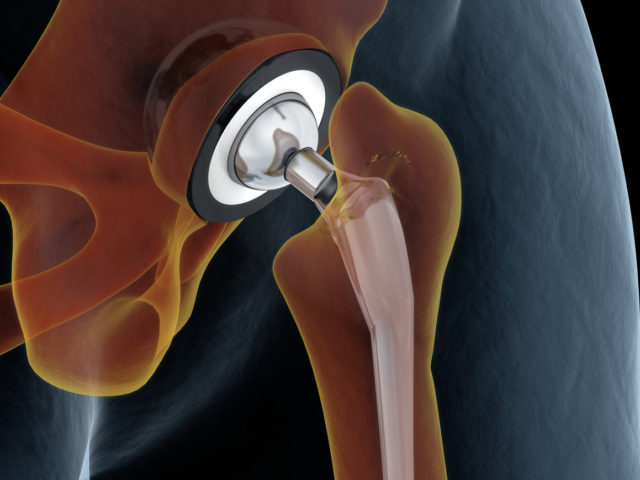

What is Hip Impingement?

A femoroacetabular impingement (FAI), more commonly known as a hip impingement, occurs with abnormal wear and tear between the ball and socket of the hip joint. When your hip is impinged, you can expect increased friction that continues to damage the joint; when tis happens you can expect pain, even when at rest or sitting…